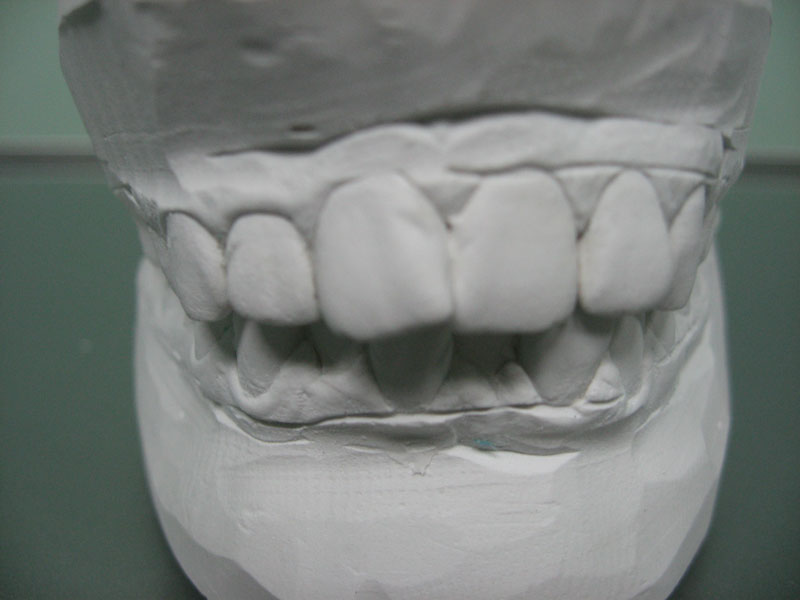

Изначально проводится диагностика. Это осмотр ортодонтом, опрос пациента, сбор анализов и оценка состояния с помощью специальных аппаратов. Чтобы определить разновидность отклонения прикуса, делается телерентгенография. На основе ее результатов изготавливается и исследуется гипсовый слепок челюсти пациента. Чтобы правильно оценить состояние жевательного аппарата, делают реографию, томографию и электромиографию.

Фото 5. Изготовление слепков челюстей пациента помогает выбрать наиболее эффективный метод лечения прикуса.